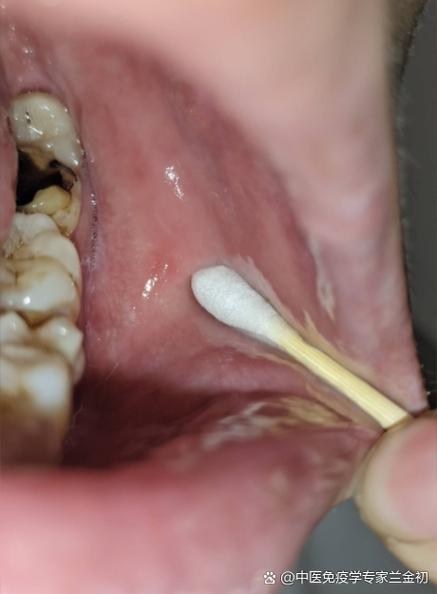

口腔后壁白色物是何物?需警惕吗?

- 扁桃体结石: 这是最常见的原因之一,扁桃体(位于喉咙两侧)的隐窝里容易积聚食物残渣、脱落的细胞和细菌,这些物质会钙化、变硬,形成白色的或黄白色的颗粒,有时会有臭味,它们可能单个存在,也可能成簇出现。

- 淋巴滤泡增生: 咽后壁和扁桃体周围有丰富的淋巴组织,在对抗感染时会增生、肿大,形成白色或黄色的小点或小颗粒,这通常是身体在对抗病毒或细菌感染时的反应,在感冒或咽炎后常见。

- 食物残渣: 刚吃完饭,食物残渣可能会卡在扁桃体隐窝或喉咙的褶皱里,看起来就是白色的“小点”或“片状物”。

- 链球菌性咽炎(俗称“化脓性扁桃体炎”): 由链球菌感染引起,除了喉咙痛、发烧外,扁桃体上会出现白色或黄色的脓点,有时甚至有脓性分泌物覆盖,这是需要抗生素治疗的典型情况。

- 真菌感染(如鹅口疮): 虽然在婴儿中更常见,但免疫力低下的人群也可能在口腔后部(包括咽喉)出现白色奶酪状或凝乳状的斑块,不易擦去,擦去后下方会有红色创面。

- 口腔黏膜白斑: 这是一种癌前病变,表现为口腔黏膜上的白色斑块,表面粗糙,不易擦掉,与长期吸烟、饮酒、咀嚼槟榔等刺激因素有关,如果发现后部黏膜出现固定的、长期不退的白色斑块,需高度警惕。